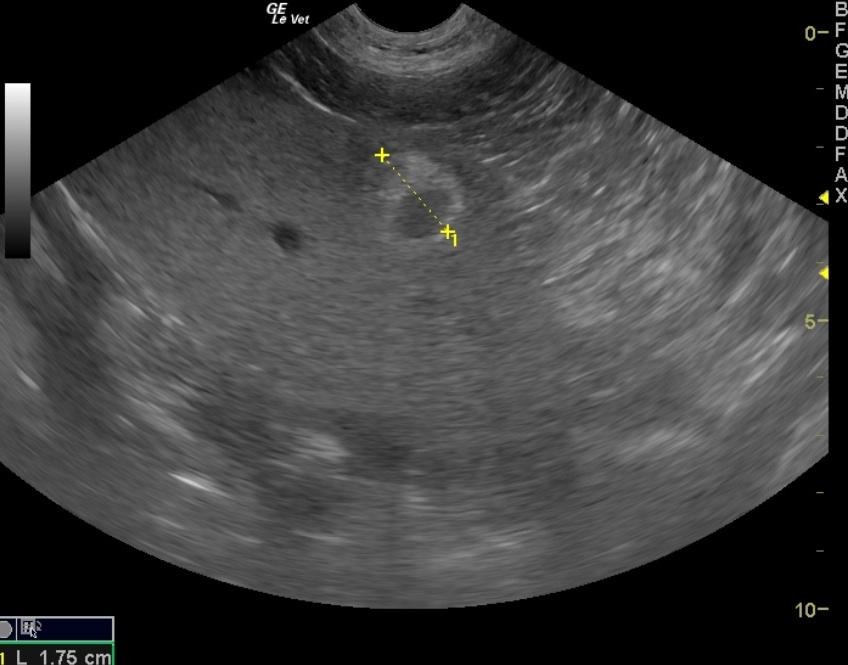

A 10 year old SF Labrador was presented with a history of not doing right and having an ACTH stimulation test at the low end of normal. Additional history was that she would vomit when taken off a chicken/rice diet. Current therapy was Pepcid. Abnormalities on urinalysis were inappropriate SG, proteinuria, pyuria, and the presence of cocci and triple phosphate crystals Abnormalities on serum biochemistry were hyperkalemia and elevated ALP activity. T4 was low. Survey radiographs were within normal limits. The patient was treated with Cerenia following another bout of vomiting.